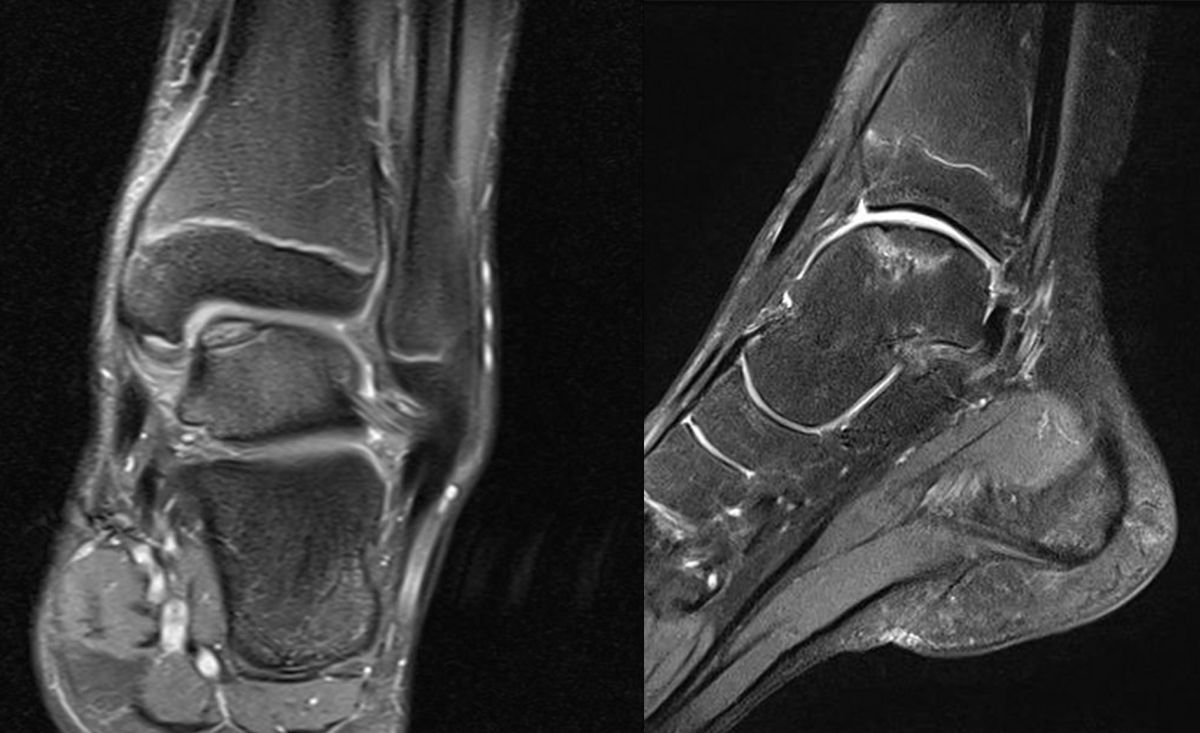

MRT

Die Kernspintomographie hat ihre Stärke in der Darstellung von Weichteilverletzungen. Insbesondere Verletzungen der Wachstumsfuge, des Periosts und der Bänder lassen sich gut visualisieren. Nachteilig ist die Untersuchungsdauer von 20-30 Minuten. Bleibt das Kind während dieser Zeit nicht ruhig liegen, kommt es zu Bewegungsartefakten, welche die Beurteilbarkeit der Bilder beeinträchtigen.

Fugengelenkfrakturen treten typischerweise vor dem 10. Lebensjahr auf, in einer Phase, in welcher die Wachstumsfugen noch weit offen sind. Dieser Frakturtyp betrifft fast ausschließlich den medialen Malleolus. Laterale Frakturen sind extrem selten, teilweise kommt es zu lateralen Bandverletzungen oder Fugenschaftfrakturen der distalen Fibula. Die Frakturlinie verläuft in einer Verlängerungslinie von der medialen Taluskante nach proximal. Häufig stellen sich Verletzungen des Innenknöchels im Röntgenbild schlechter dar, insbesondere wenn die Aufnahmen verdreht sind oder die Ebene der Fraktur bei geringer Dislokation verkippt zur Röntgenebene liegt. Besteht klinisch der geringste Hinweis auf eine Verletzung des Innenknöchels, muss aufgrund der Tragweite der Verletzung durch entsprechende Aufnahmen gegebenenfalls auch Schnittbildverfahren die Verletzung sicher diagnostiziert oder ausgeschlossen werden (Abb. 15).